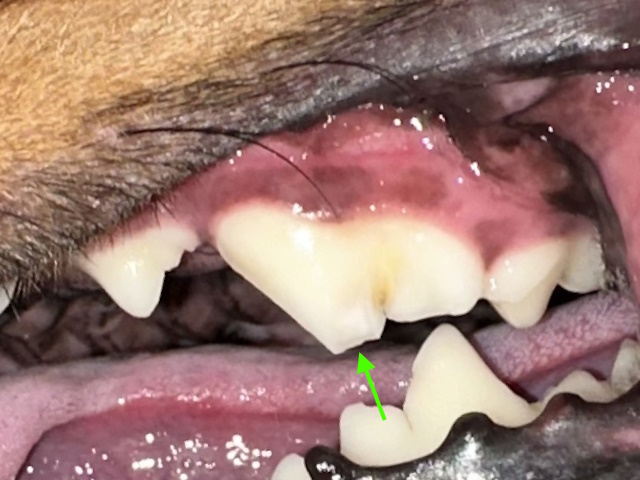

An uncomplicated crown fracture that caused exposure of dentin (green arrow), but not the pulp.